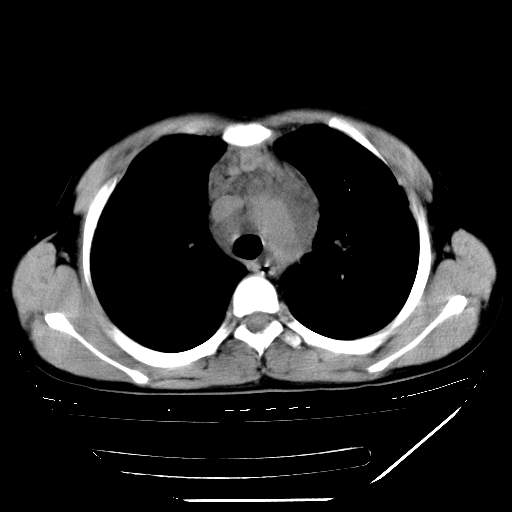

男,13岁,咳嗽、咳痰伴发热一周。

中上纵隔见多枚淋巴结肿大,部分相互融合成团片,左肺门增大,上叶支气管变窄,肺内多处斑片状 索条状及棉絮状致密影。临床“男,13岁,咳嗽、咳痰伴发热一周。”首先考虑:原发综合征!不除外淋巴瘤可能!

纵隔多发肿大淋巴结,部份有融合改变。双肺血管气管束增厚,以肺门为中心向外周散发,以左肺下叶为明显。考虑淋巴瘤可能性大。不除外原发综合征。

中上纵隔见多枚淋巴结肿大,部分相互融合成团片,左肺门增大,上叶支气管变窄,左肺支气管血管束增粗,可见磨玻璃样影。临床“男,13岁,咳嗽、咳痰伴发热一周。”首先考虑:淋巴瘤可能性大!

中上纵隔见多枚淋巴结肿大,部分相互融合成团片,纵隔内脂肪间隙模糊,左肺门增大,上叶支气管变窄,左肺支气管血管束增粗,可见磨玻璃样影。考虑纵隔淋巴管炎